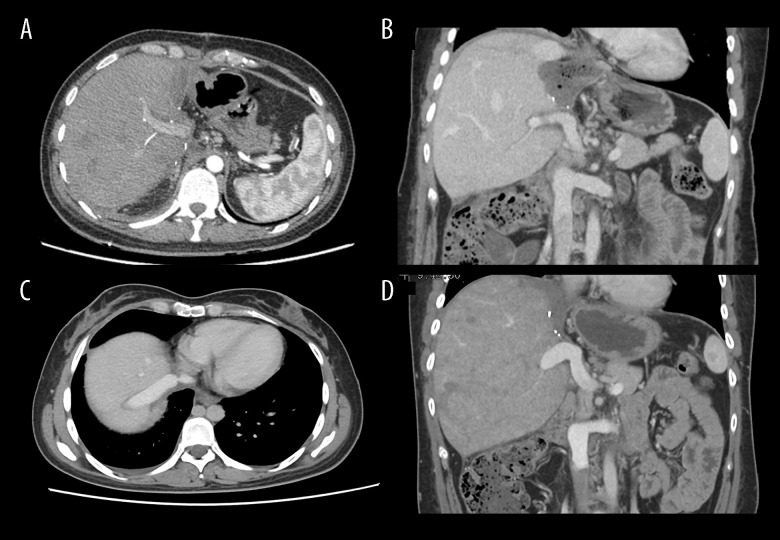

BACKGROUND Alveolar echinococcosis, a lethal parasitic disease, can invade important vessels in the liver. A liver vascular anomaly causes compensatory changes in other blood vessels connected to it because of the close relationship between them. Obstruction of the retrohepatic inferior vena cava and the second hilum can form the intrahepatic venous network and the vertebral venous plexus pathway, which can be demonstrated by hepatic venography and anatomical and autopsy studies. CASE REPORT A Tibetan woman, age 31, with hepatic alveolar echinococcosis and unique intrahepatic hemodynamic features, was referred to our center and underwent successful ex vivo liver resection and autotransplantation. We report our experience and review the literature. In this clinical case, we performed an ex vivo liver resection and autotransplantation without hepatic inferior vena cava reconstruction. After surgery, the circulatory system hemodynamic remained stable, and blood flow in the liver and trunk was unhindered. The patient underwent an uneventful hospitalization and recovery. CONCLUSIONS This clinical case demonstrates the unique venous access, hemodynamic alterations, and surgical decision-making that follow the invasion of significant hepatic vessels by alveolar echinococcosis lesions. HAE exhibits unique collateral vessels, which are uncommon in other diseases. Additionally, this kind of therapy offers fresh perspectives for the surgical treatment of end-stage HAE.